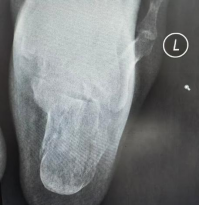

案例1:患者42岁,因高坠伤致左跟骨骨折、伴活动受限9小时入院。入院诊断:左跟骨骨折。入院后,科室采用3D打印导板辅助下行经皮跟骨骨折闭合复位内固定术,通过导入患者跟骨CT数据完成三维重建,在计算机上进行虚拟复位并精准规划出用于固定骨折块的最佳“虚拟螺钉”路径的进针点、角度及深度,以安全地穿过骨折块并达到最大把持力;再将计算机中的“虚拟路径”转移到患者体表,依据规划好的钉道,生成一个能与患者足跟外侧皮肤及骨骼解剖标志(如跟骨结节、腓骨远端等)完美贴合的个性化手术导板。术中只需将灭菌后的个性化导板准确贴合在患者足跟外侧预定的皮肤位置,借助导板导向孔直接钻入导针,实现了置钉精准化、手术微创化与效率提升的多重目标,最大程度保护了局部软组织血运,降低了伤口并发症风险。

(术前)